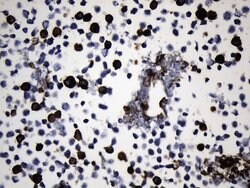

EGFR L858R Mouse anti-Human, Clone: UMAB234, lyophilized, UltraMAB™

EGFR (Epidermal growth factor receptor, HER1, ErbB1) is encoded by the EGFR gene located on chromosome 7 in humans. EGFR belongs to the HER/ERbB family of proteins that includes three other receptor tyrosine kinases, ERbB2, ERbB3, ERbB4. EGFR is a transmembrane receptor and binding of its cognate ligands such as EGF (Epidermal Growth Factor) and TGF alpha (Transforming Growth Factor alpha) to the extracellular domain leads to EGFR dimerization followed by autophosphorylation of the tyrosine residues in the cytoplasmic domain. Phosphorylation of EGFR at certain residues is also mediated by Src-non-receptor kinase. EGFR activation signals multiple downstream signaling cascades such as the Ras - ERK, PI3-K - Akt, Jak - STAT and PKC pathways that help in growth and proliferation of cells. Phosphorylation of EGFR at Y1086 specifically allows binding of the adaptor protein GRB2, leading to activation of the MAPK pathway. Upon receptor activation and signaling, EGFR is endocytosed and targeted for degradation or recycling. Mutations in the EGFR gene are associated with lung cancer and multiple alternatively spliced transcript variants encode different protein isoforms of EGFR have been found. Increased production or activation of EGFR has been associated with poor prognosis in a variety of tumors. Moreover, EGFR overexpression is observed in tumors of the head and neck, brain, bladder, stomach, breast, lung, endometrium, cervix, vulva, ovary, esophagus, stomach and in squamous cell carcinoma. This product is specific for EGFR (mutant L858R).Specifications

| Immunohistochemistry (Paraffin) | |

| Synthetic peptide around the L858R mutation region of the human EGFR conjugated to KLH | |